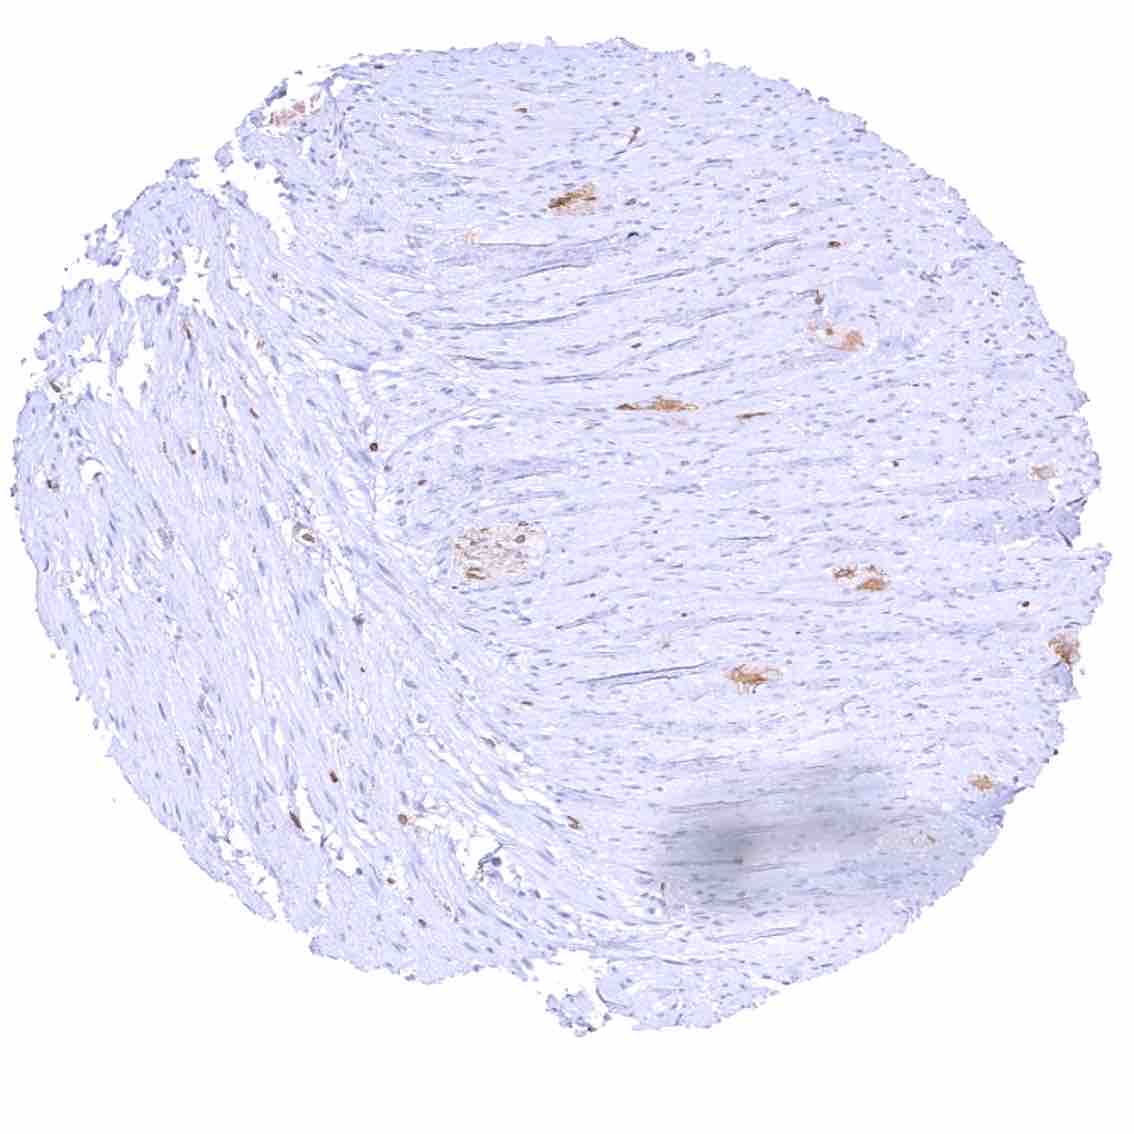

Urinary bladder, muscular wall